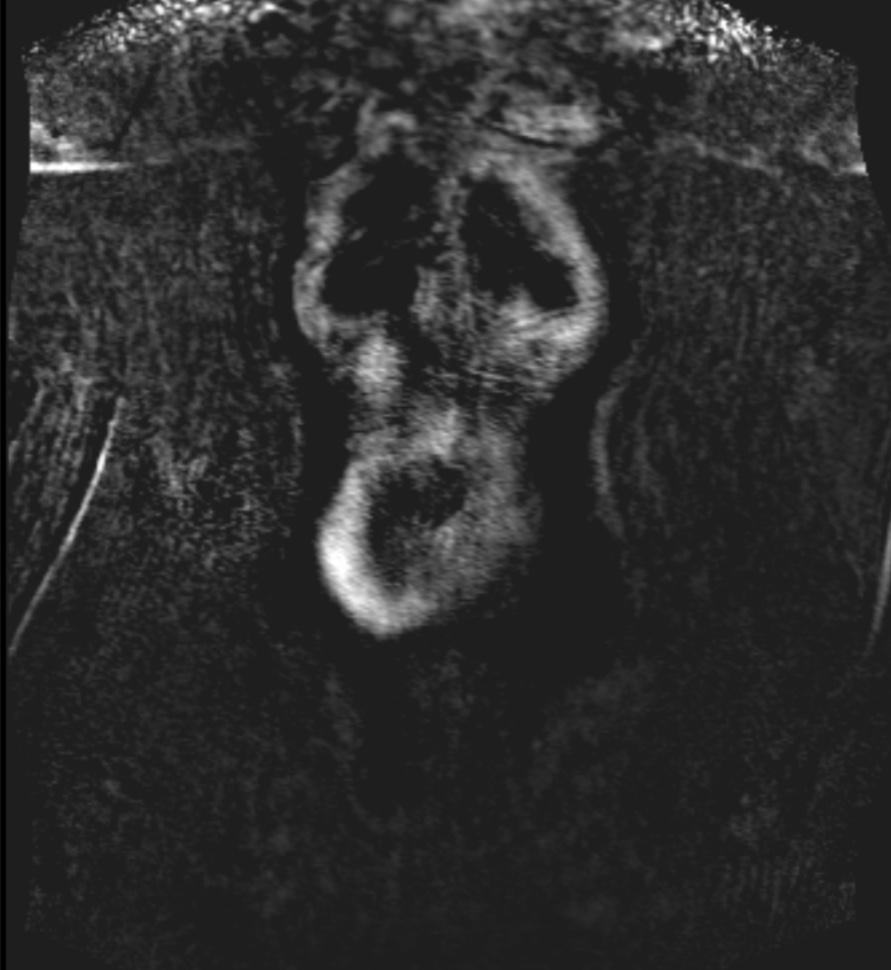

AnonymDiskusjon Skrevet 13. november 2018 Skrevet 13. november 2018 Har tatt MR av abdomen, bekken og bein/underekstremiteter av blodårer i går, og så dette bildet her, hva er dette og hvor er det? Ser ut som blodpropp? Setter stor pris på svar! Anonymous poster hash: 5e40b...411